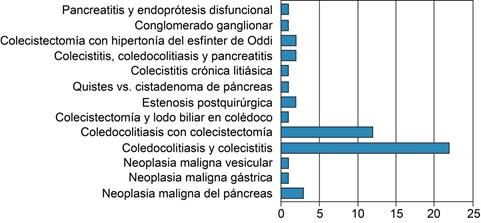

Las causas benignas fueron: la coledocolitiasis asociada a colecistitis en 22 casos (44%) fue la primera, seguida de coledocolitiasis asociada con colecistectomía con 12 casos (24%). Otras causas fueron colecistitis con coledocolitiasis asociadas con pancreatitis en dos casos (4%), siguiendo con un caso colecistitis crónica litiásica y un quiste vs. cistadenoma de páncreas (Tabla 1).

Tabla 1: Causas de obstrucción de la vía biliar, la principal es la coledocolitiasis asociada o no a colecistectomía. El principal grupo etario fue de 61 a 80 años en patologías benignas y de 41 a 60 años en patologías malignas.

| Etiología | Grupo etario más frecuente (años) | Total de pacientes |

|---|---|---|

| Neoplasia del páncreas | 41 a 60 | 3 |

| Neoplasia gástrica | 61 a 80 | 1 |

| Neoplasia vesicular | 61 a 80 | 1 |

| Coledocolitiasis y colecistitis | 20 a 40 | 22 |

| Coledocolitiasis con colecistectomía | 61 a 80 | 12 |

| Colecistectomía y lodo biliar en colédoco | 61 a 80 | 1 |

| Estenosis postquirúrgica | 41 a 80 | 2 |

| Quistes versus cistadenoma de páncreas | 41 a 80 | 1 |

| Colecistitis crónica litiásica | 41 a 60 | 1 |

| Colecistitis, coledocolitiasis, pancreatitis | 61 a 60 | 2 |

| Colecistectomía con hipertonía del esfínter de Oddi | 61 a 80 | 2 |

| Conglomerado ganglionar | 20 a 40 | 1 |

| Pancreatitis, endoprótesis disfuncional | 41 a 60 | 1 |

| Total | 50 |

De las causas malignas, la principal fue el carcinoma de la cabeza del páncreas con tres casos (6%), seguidos de un caso de neoplasia gástrica, una neoplasia vesicular y un conglomerado ganglionar secundario a cáncer de ovario.

La principal causa de obstrucción intraluminal benigna fue la coledocolitiasis asociada o no a colecistectomía (Figura 1). Las causas extraluminales son las menos frecuentes y son ocasionadas principalmente por patologías malignas condicionantes de efecto de masa en la vía biliar; las principales causas reportadas fueron la neoplasia pancreática (Figura 2), seguida de la neoplasia gástrica y conglomerados ganglionares. Dentro de las causas benignas de obstrucción extraluminal se encontraron: hipertonía del esfínter de Oddi y pancreatitis.